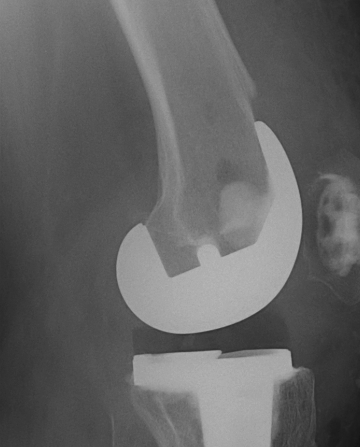

4.  Revision TKR

Indications

- very distal fracture

- insufficient bone stock

- loose prosthesis

Components

- stemmed, constrained implant

- tumour prosthesis